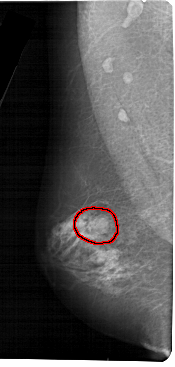

ics_version 1.0 filename A-1317-1 DATE_OF_STUDY 9 3 1992 PATIENT_AGE 68 FILM FILM_TYPE REGULAR DENSITY 4 DATE_DIGITIZED 28 7 1998 DIGITIZER HOWTEK 43.5 SEQUENCE LEFT_CC LINES 5146 PIXELS_PER_LINE 2236 BITS_PER_PIXEL 12 RESOLUTION 43.5 OVERLAY LEFT_MLO LINES 5491 PIXELS_PER_LINE 2611 BITS_PER_PIXEL 12 RESOLUTION 43.5 OVERLAY RIGHT_CC LINES 5281 PIXELS_PER_LINE 2341 BITS_PER_PIXEL 12 RESOLUTION 43.5 NON_OVERLAY RIGHT_MLO LINES 5491 PIXELS_PER_LINE 2911 BITS_PER_PIXEL 12 RESOLUTION 43.5 NON_OVERLAY |

FILE: A_1317_1.LEFT_CC.OVERLAY TOTAL_ABNORMALITIES 1 ABNORMALITY 1 LESION_TYPE MASS SHAPE ROUND MARGINS CIRCUMSCRIBED ASSESSMENT 4 SUBTLETY 3 PATHOLOGY BENIGN TOTAL_OUTLINES 1 BOUNDARY |